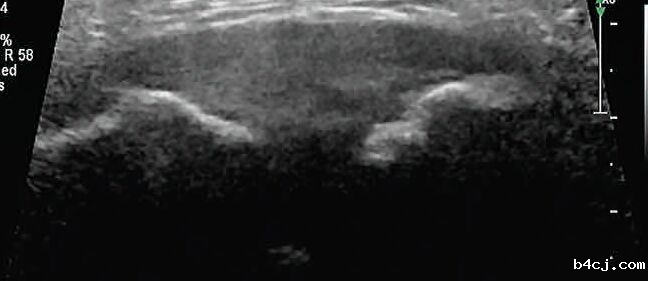

周女士怀孕已经39周了,但作为一个即将迎接新生命的准妈妈来说,她最近却高兴不起来。因为耻骨联合部位走路时痛,上下车、上下楼梯时会更痛,甚至在床上翻身和起床都有困难。于是,在家人的陪伴下,她来到了我院就诊。医生通过对周女士的耻骨联合超声检查发现,其耻骨联合部位明显分离达到了15mm,这就是其疼痛的原因。

耻骨联合分离常用的诊断方法为X射线、CT或MIR检查,但这些检查方法对孕期胎儿均有一定的影响或者价格昂贵,孕妇较难接受。超声作为一种安全、无创、准确的检查方法,可为耻骨联合分离诊断提供较准确的依据,值得在临床推广应用。如孕期或产后出现耻骨联合部位疼痛等相关症状时,可进行超声检查明确诊断,同时咨询产科和产后康复医师给予专业指导和对症治疗。